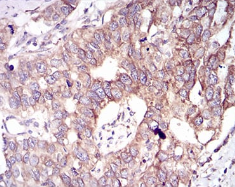

IHC    1/200 - 1/1000